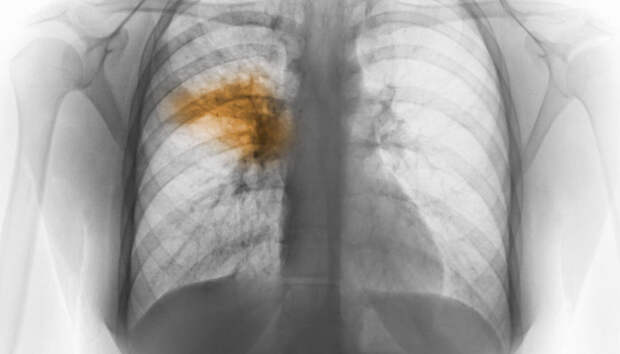

Всем пациентам с воспалением легких неоднократно проводится исследование на COVID-19 Девять человек за сутки госпитализированы с внебольничной пневмонией в Карелии, сообщает оперштаб по борьбе с распространением коронавирусной инфекции. Летальных исходов за прошедшие 24 часа в республике не зафиксировано.

Начиная с 1 апреля, с внебольничной пневмонией госпитализированы 1455 пациентов, 80 человек умерли (с учетом пациентов, госпитализированных […]